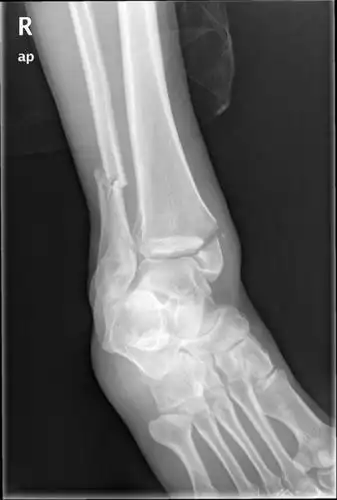

右内外踝骨折